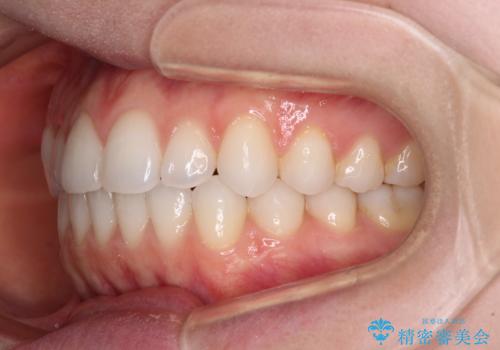

上下前歯が接触しない オープンバイトをインビザラインで改善

- 前歯の上下スペースによる食べにくさを気にして来院された患者様です。

インビザラインにより上下の前歯の隙間を閉じていくこととしました。

上下の奥歯を圧下させるようにすることで、前歯を接触させるように計画しました。

上下の隙間に舌が入り込むことがオープンバイトの原因であったため、舌の筋肉のトレーニングも並行して行い、後戻りの抑制を図りました。